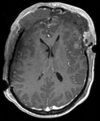

Within Exam:

Exam 1 GRE aligned to T1